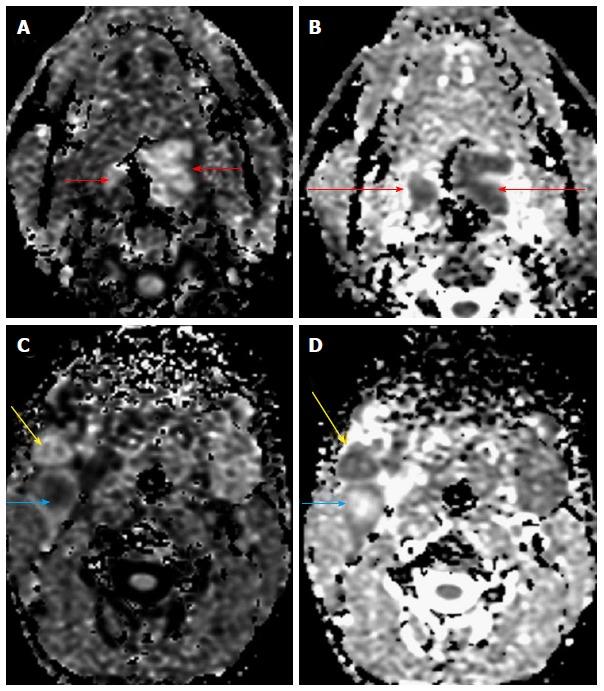

"Personalized oncology" is a multi-disciplinary science, which requires inputs from various streams for optimal patient management. Humongous progress in the treatment modalities available and the increasing need to provide functional information in addition to the morphological data; has led to leaping progress in the field of imaging. Magnetic resonance imaging has undergone tremendous progress with various newer MR techniques providing vital functional information and is becoming the cornerstone of "radiomics/radiogenomics". Diffusion-weighted imaging is one such technique which capitalizes on the tendency of water protons to diffuse randomly in a given system. This technique has revolutionized oncological imaging, by giving vital qualitative and quantitative information regarding tumor biology which helps in detection, characterization and post treatment surveillance of the lesions and challenging the notion that "one size fits all". It has been applied at various sites with different clinical experience. We hereby present a brief review of this novel functional imaging tool, with its application in "personalized oncology".

“个性化肿瘤学”是一门多学科科学,为实现最佳的患者管理,需要各个领域的投入。现有治疗方式取得了巨大进展,除形态学数据外,提供功能信息的需求也日益增加,这推动了成像领域的飞跃发展。磁共振成像随着各种更新的磁共振技术取得了巨大进步,这些技术提供了至关重要的功能信息,并正成为“放射组学/放射基因组学”的基石。扩散加权成像就是这样一种技术,它利用了水质子在给定系统中随机扩散的趋势。这项技术通过提供有关肿瘤生物学的重要定性和定量信息,彻底改变了肿瘤成像,有助于病变的检测、特征描述和治疗后监测,挑战了“一刀切”的观念。它已在不同部位应用,并积累了不同的临床经验。在此,我们简要综述这一新型功能成像工具及其在“个性化肿瘤学”中的应用。